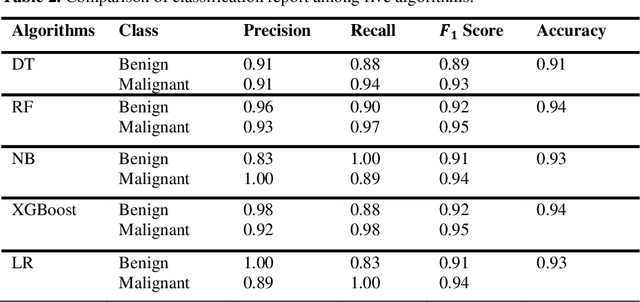

Nowadays, Breast cancer has risen to become one of the most prominent causes of death in recent years. Among all malignancies, this is the most frequent and the major cause of death for women globally. Manually diagnosing this disease requires a good amount of time and expertise. Breast cancer detection is time-consuming, and the spread of the disease can be reduced by developing machine-based breast cancer predictions. In Machine learning, the system can learn from prior instances and find hard-to-detect patterns from noisy or complicated data sets using various statistical, probabilistic, and optimization approaches. This work compares several machine learning algorithm's classification accuracy, precision, sensitivity, and specificity on a newly collected dataset. In this work Decision tree, Random Forest, Logistic Regression, Naive Bayes, and XGBoost, these five machine learning approaches have been implemented to get the best performance on our dataset. This study focuses on finding the best algorithm that can forecast breast cancer with maximum accuracy in terms of its classes. This work evaluated the quality of each algorithm's data classification in terms of efficiency and effectiveness. And also compared with other published work on this domain. After implementing the model, this study achieved the best model accuracy, 94% on Random Forest and XGBoost.